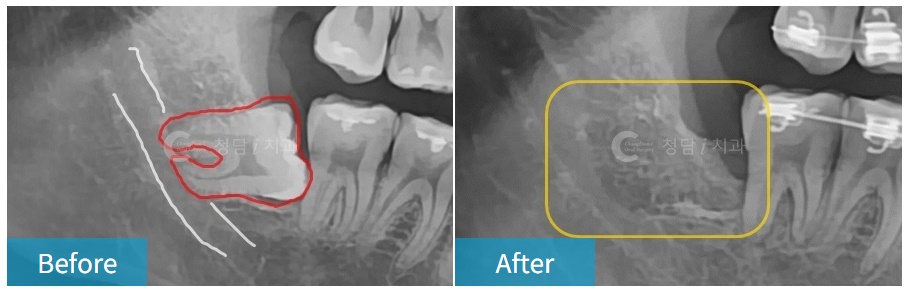

매복 사랑니, 신경과 가깝거나 엑스레이에 중첩되어 보이는 사랑니,

뿌리가 휘어있는 사랑니, 거꾸로 누워있는 사랑니 등

수많은 케이스를 안전하게 발치해온 숙련도 높은 구강외과의입니다.

사랑니 발치는 단순히 이를 뽑는 행위가 아닙니다.

치조골의 구조, 신경관 위치, 치아의 각도 등을 정확히 파악하고,

주변의 뼈 손상을 최소화하며 빠르게 뽑아야 환자의 고통을 줄일 수 있기 때문에

풍부한 임상 경험과 숙련도가 있는 전문의에게 뽑는 것이 중요하지요.

내원하시면 X-ray와 CT 촬영 후 신경과의 거리, 뿌리의 방향 등을 분석한 후 발치를 진행하게 됩니다.